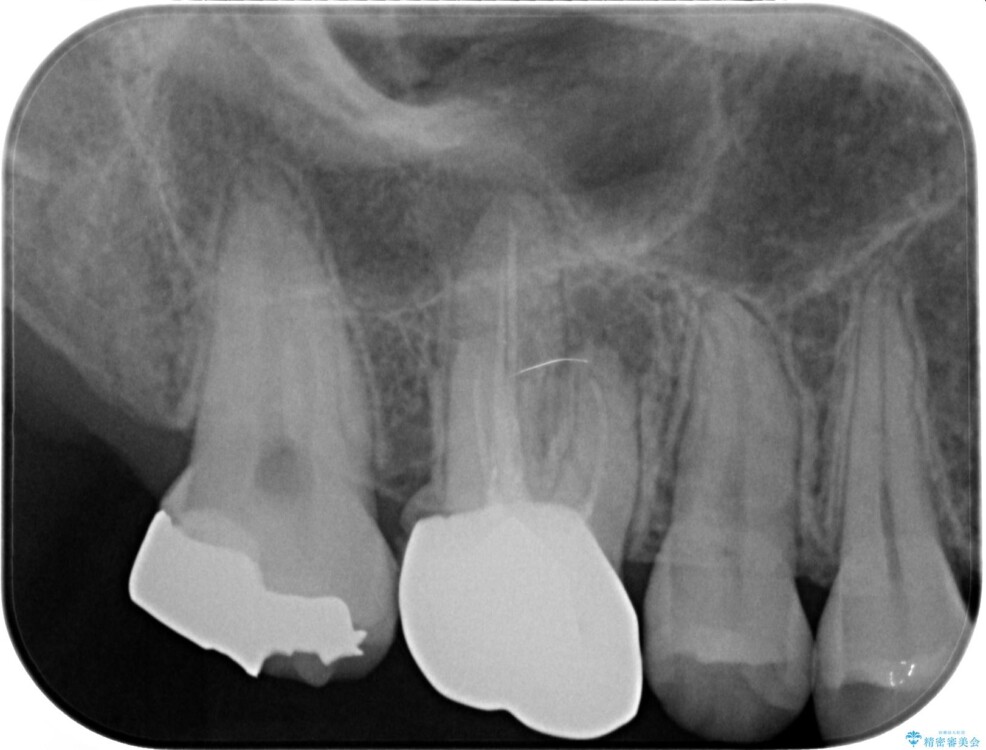

インプラント希望部位は右下第一大臼歯と第二大臼歯です。

しかし、噛み合わせの相手である右上の第二大臼歯が、長期間噛み合う歯がなかった影響で**挺出(歯が下に伸びてくる状態)してしまっており、このままではインプラントを埋入して被せもの(上部構造)を入れるためのスペースが不足している状態でした。

• 挺出歯を圧下してスペースを確保!目立たない部分矯正で下顎大臼歯にインプラント治療を実現 治療前画像